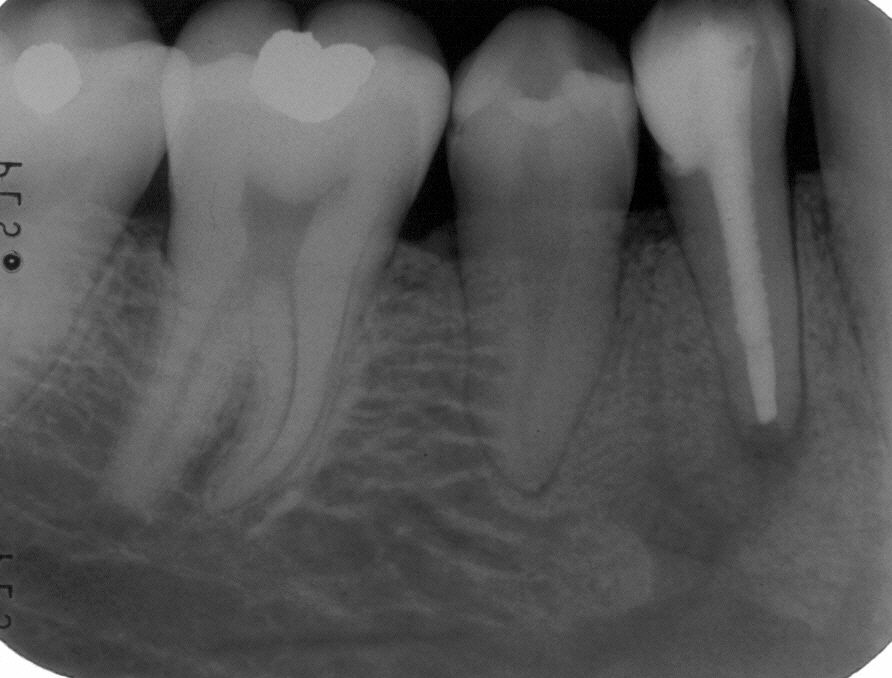

Wurzelfüllung im April 1996 in lateraler Kondensation mit normierter Guttapercha und AH 26

Zustand nach adhäsiver Insertion

Zustand nach adhäsiver Insertion eines Titanstiftes im Januar 1997 also neun Monate nach Wurzelfüllung unmittelbar vor Eingliederung eines Langzeitprovisoriums. Die Ausheilungstendenz auf nur konservativem Wege ist deutlich sichtbar